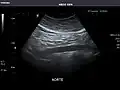

Aorta: Visualized portions normal in caliber, 16 x 15 mm.

It can be used on the abdominal aorta to detect or exclude abdominal aortic aneurysm. For this purpose, the standard aortic measurement for abdominal aortic aneurysm is between the outer margins of the aortic wall.[4]

Aorta -